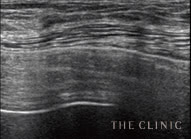

実際のエコー画像

治療後